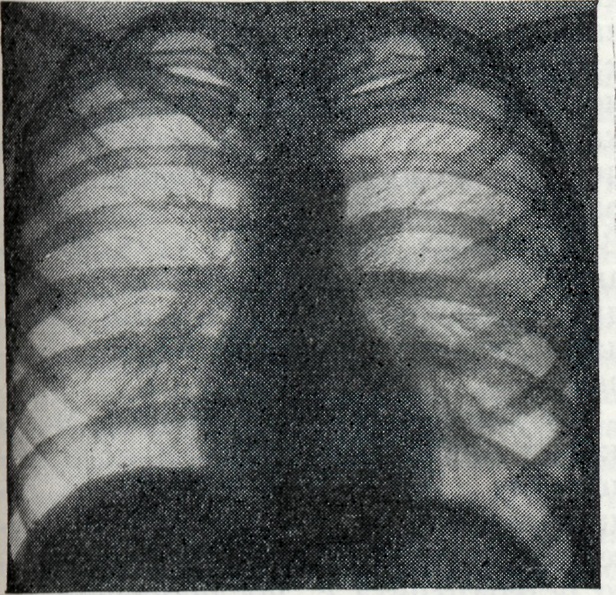

Однако широкое применение рентгенологического исследования больных Б. показало, что и в фазах генерализации инфекции, и в латентном периоде встречаются также бруцеллезный внутригрудной лимфаденит (рисунок 5 и 6), бронхопневмонии и плевриты бруцеллезного происхождения.

Лимфаденит при Б. проявляется рентгенологически в виде гиперплазии лимф, узлов корней лёгких, нередко с прикорневой инфильтрацией тяжистого или диффузного характера. Наблюдается как двустороннее, так и одностороннее поражение. В клинико-рентгенологическом аспекте следует иметь в виду быстрое возникновение, но очень медленное обратное развитие подобных изменений, что, впрочем, относится ко всем изменениям в лёгких при Б. В отличие от таких заболеваний, как саркоидоз, увеличение лимф. узлов при Б. не даёт картины резких полициклических бугристостей, прикорневая инфильтрация в начале процесса носит диффузный характер, свойственный скорее прикорневой инфильтрации при туберкулёзе, чем при болезни Бека. Признаки бронхостеноза при этом отсутствуют. Дифференциальная диагностика с лимфогранулематозом и ретикулосаркоматозом на основании одних лишь рентгенологических данных затруднительна и должна базироваться на картине крови, реакциях Райта, Хаддлсона и Бюрне.

Информация об Ordo Deus Перейти в оглавление сайта

Рис. 6.

Левосторонний бронхаденит при бруцеллёзе в фазе генерализации инфекции.